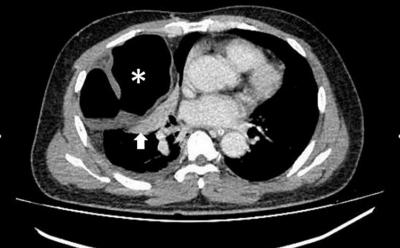

CT in axial view at the level of thorax with evidence of herniated bowel loop into the right thoracic cavity (*) complicated with collapse consolidation of the adjacent lung (arrow)